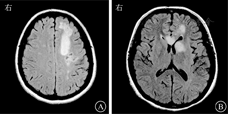

患者女,27岁,因"间断发热、头痛11个月,肢体麻木、纳差1 d"于2015年5月29日收治武汉市医疗救治中心。2014年5月患者因原发性不孕行体外受精-胚胎移植术,其后间断低热,8月下旬经超声检查提示死胎,即在外院行清宫术。9月下旬发热症状再次加重,在外院经抗感染治疗后一度好转。11月初患者再次出现发热,体温多在39 ℃左右,伴头痛、呕吐,经青霉素640万U,2次/d抗感染治疗后未见好转。反复在外院就诊,2014年11月9日行腰椎穿刺查脑脊液结果示白细胞计数55×106/L,乳酸脱氢酶35 U/L,总蛋白2 278 mg/L(表1);结核感染T淋巴细胞斑点试验阳性。11月10日行头颅MRI提示脑干、双侧小脑半球、双侧额叶及右侧颞叶异常强化灶(图1),诊断为结核性脑膜脑炎。彩色多普勒超声示子宫壁多发性钙化灶,子宫后壁囊性包块,考虑合并生殖系统结核。否认既往特殊病史。婚育史:患者20岁结婚,婚后7年内未避孕情况下未能正常受孕。予异烟肼0.4 g/d、利福平0.45 g/d、吡嗪酰胺1.25 g/d联合抗结核治疗后病情渐有好转,除吡嗪酰胺治疗5个月后停药外,其余药物持续应用于整个抗结核疗程中。2015年5月28日患者突发急性脑梗死,表现为吐词不清、左上肢乏力,遂入院治疗。6月2日复查头颅MRI见新发脑梗死病灶,但脑膜强化减轻(图2),6月5日查脑脊液相关指标好转(表1),加强抗结核治疗(异烟肼0.4 g/d、利福平0.6 g/d、吡嗪酰胺1.5 g/d、对氨基水杨酸钠8.0 g/d、阿米卡星0.6 g/d、左氧氟沙星0.6 g/d),辅以脱水、抗感染等治疗后好转出院。2015年7月19日患者突发运动性失语进行性加重,右侧肢体麻木,活动受限,伴有胸闷、气促,感疲乏无力,再次就诊,头颅MRI提示颅脑梗死病灶较前明显,但脑膜强化较前减轻(图3),2015年7月22日再次查脑脊液结果示总蛋白441.4 mg/L,白细胞计数、氯化物、葡萄糖等指标无异常(表1)。体格检查:神志清楚,反应稍迟钝;颈软,颈动脉搏动正常,双侧颈动脉未闻及血管杂音;双侧瞳孔等大等圆,对光反射灵敏,右眼外展不到边;伸舌右偏;右侧上肢肌力4+级,右下肢肌力4级,右侧Babinski征阳性,Kernig征阴性,右侧腱反射亢进,提示右侧肢体偏瘫。进一步行头颅磁共振血管成像(magnetic resonance angiography, MRA)示双侧大脑前、中动脉不显影、侧支循环增粗紊乱,Willis环特征性改变符合烟雾病(图4)。继续完善实验室检查,结核蛋白芯片检测38 000蛋白、脂阿拉伯甘露糖及结核分枝杆菌抗体-IgG均阳性,结核感染T淋巴细胞斑点试验阳性,抗核抗体谱2、抗中性粒细胞胞浆抗体、梅毒螺旋体抗体阴性;颈动脉彩色多普勒超声无异常;肿瘤标志物阴性;一次脑脊液抗酸染色阳性,因此排除其他感染、占位等因素,再次确认结核感染诊断,综合以上结果,诊断为结核性脑膜脑炎合并烟雾病。维持原方案抗结核治疗,并给予甘露醇稳定颅内压、地塞米松、吲哚布芬抗感染、营养神经、改善脑循环及防治血管性痴呆等治疗,患者脑梗死相关症状逐渐好转,肢体功能恢复,生活可以自理,而后出院继续服药治疗,治疗过程中定期复查腰椎穿刺脑脊液检查及头颅MRI检查等,抗结核治疗2年后复查头颅MRI提示脑膜强化等基本吸收(图5),抗结核治疗2年满疗程停药。